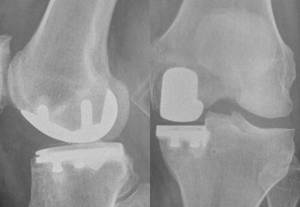

Hoe meer ervaring met halve knieprotheses, hoe minder kans op complicaties